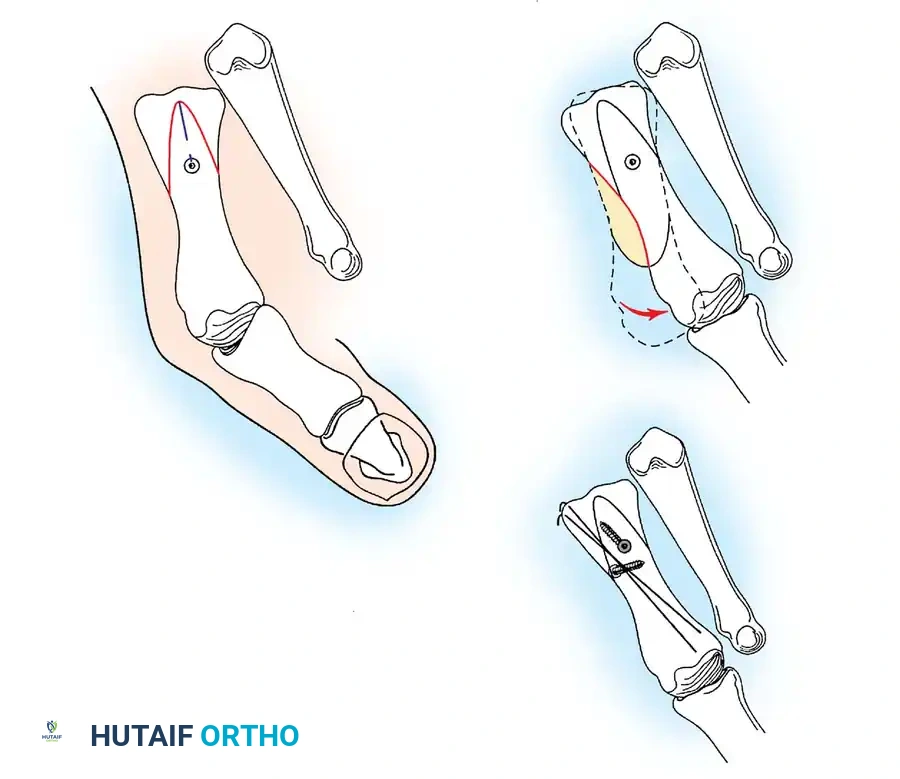

Two other anatomical variants involving the articular surface of the fi rst metatarsophalangeal joint can lead to hallux valgus. In the fi rst variant, the articular surface of the metatarsal head is offset, resembling a scoop of ice cream sitting at an angle on a cone (Fig. 78-6). This has been described as the distal metatarsal articular angle (see Fig. 78-8). In the second, the articular angle of the base of the proximal phalanx in relation to its longitudinal axis is offset. This has been described as the phalangeal articular angle. Although the normal range of these angles is generally considered to be 7 to 10 degrees for the phalangeal articular angle and 10 to 15 degrees for the distal metatarsal articular angle, exact measurements are diffi cult to reproduce because of the variability of radiographic and measurement techniques. Increasing evidence indicates, however, that the failure to correct these two deformities, especially the distal metatarsal articular angle, can cause unsatisfactory results after surgery in some patients. Forceful straightening of the hallux should be avoided if it sacrifi ces tarsalgia. The entire forefoot must be evaluated for these multiple components of hallux valgus before surgical planning is complete and recommendations can be made to the patient. The controversy continues over which deformity is the essential lesion in hallux valgus: metatarsus primus varus or lateral deviation of the great toe. Each is incriminated as the cause of the other. The strongest data probably support lateral deviation of the great toe as the primary deformity in most patients, followed by medial angulation of the fi rst metatarsal, but metatarsus primus varus may be the principal cause in adolescents. Further controversy surrounds the role of footwear as the prime offender in the development of hallux valgus. Most orthopaedic surgeons have seen unilateral hallux valgus when both feet are clinically and radiographically the same structurally except that one foot has a bunion deformity and the other foot is normal. Evidence supports that hallux valgus may be familial, especially when it occurs in adolescents. Although no study of shod and unshod societies has implicated inappropriate footwear as the sole cause of hallux valgus, after genetic factors, binding, unphysiologically designed footwear probably is the major cause in modern societies. Hypermobility of the fi rst ray also has been suggested as a causative factor in the development of hallux valgus and fi rst metatarsal varus, but this is controversial. Coughlin and Shurnas, Myerson and Badekas, King and Toolan, and Faber et al. offer excellent discussions of this problematic area. Finally, certain anatomical and structural abnormalities almost certainly play a causative role in hallux valgus. Pronated fl atfeet, abnormal insertion of the posterior tibial tendon, increased obliquity of the fi rst metatarsomedialcuneiform joint, an abnormally long fi rst ray, incongruous articular surfaces of the fi rst metatarsophalangeal joint, and excessive valgus tilt of the articular surface of the fi rst metatarsal head and proximal phalangeal articular surface may contribute singly or in combination to the deformity and infl uence the recommended treatment. Hypertrophy of the medial eminence has been described as a component of hallux valgus deformity since the earliest reports; however, more recent investigations, including those of Thordarson and Krewer, have found that bony proliferation is not a component of the pathoanatomy of hallux valgus and that the prominence of the medial eminence results from the combination of metatarsus primus varus and medial deviation that uncovers the articular surface. Thordarson and Krewer compared radiographs of 50 feet in patients who had surgery for hallux valgus deformity with radiographs of 50 feet from a control group without hallux valgus deformity and found little difference in the average width of the medial eminence (4.4 mm and 4.1 mm). With more than 130 operations recommended for the treatment of hallux valgus, it is practical to describe only

Fig. 78-6 A, Note valgus orientation of articular surface of fi rst metatarsal head. B, After proximal metatarsal osteotomy on right foot. Sesamoid sling remains dislocated, articular surface of metatarsal head maintains valgus posture, and joint is congruous in valgus. Double osteotomy of fi rst metatarsal (proximally for varus correction and distally for valgus correction of articular surface) and soft-tissue realignment are necessary. Alternatively, arthrodesis of fi rst metatarsophalangeal joint or distal metatarsal osteotomy (chevron) can be performed. Without anatomical reduction of sesamoid sling apparatus, distal metatarsal osteotomy would fail.